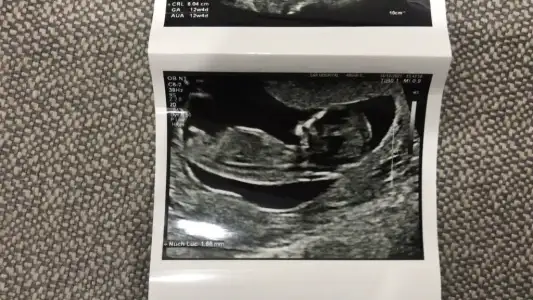

12+2 benimde 😌 yorumları bekliyorum 😌😌

Eklentiler

• 3CAD75B2-C228-4C3C-8908-9D6B17842307.webp

3CAD75B2-C228-4C3C-8908-9D6B17842307.webp

61,4 KB · Görüntüleme: 72